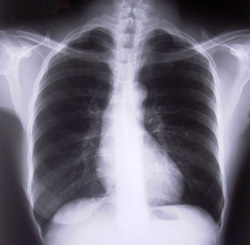

心エコーとは

心エコー(心臓超音波検査)とは、高周波数の超音波を心臓に発信し、反射波によって心臓の様子を画像に映し出して診断する検査です。現代の「突然死」の原因は、そのほとんどが心臓発作を始めとした突発性の心臓疾患となっています。心エコーならば、常に拍動している心臓の様子を画像で観察できるため、心臓の異常を早期発見するために非常に有効です。また、心エコーは保険点数が高いため、導入することで病院側としても利点が大きいという特徴があります。

心エコーでわかる病気

心肥大

拡張型心筋症

各種弁膜症

心拡大

心筋梗塞

先天性の心臓病

肺高血圧

甲状腺腫瘍 etc・・・